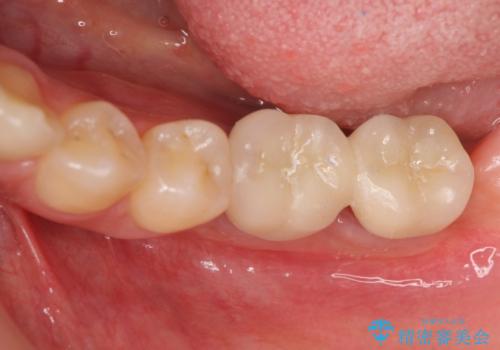

他院で断られた骨造成を伴うインプラント治療

- 虫歯を放置し他院で抜歯後、入れ歯を提案されインプラント治療を希望され来院されました。

CT画像より骨の量は少なくそのままではインプラントの埋入が難しい状態です。

骨造成を行い安定したインプラントの環境を整える治療を計画します。